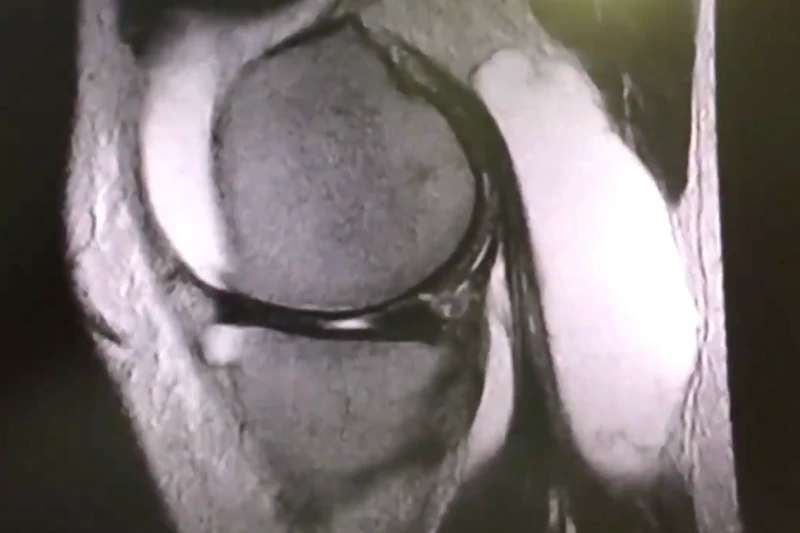

La anatomía de la huella femoral del LCA y su correcta reconstrucción son aspectos fundamentales para el éxito de la cirugía y la recuperación adecuada de la función de la rodilla.

Es la zona en la que el LCA se une a la tibia. Se encuentra en la parte interna de la articulación de la rodilla, en la tibia proximal.

El ligamento cruzado posterior es más ancho y fuerte que el ligamento cruzado anterior. Entra para saber más.